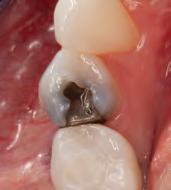

DISTO-OCCLUSAL CLINICAL CASE